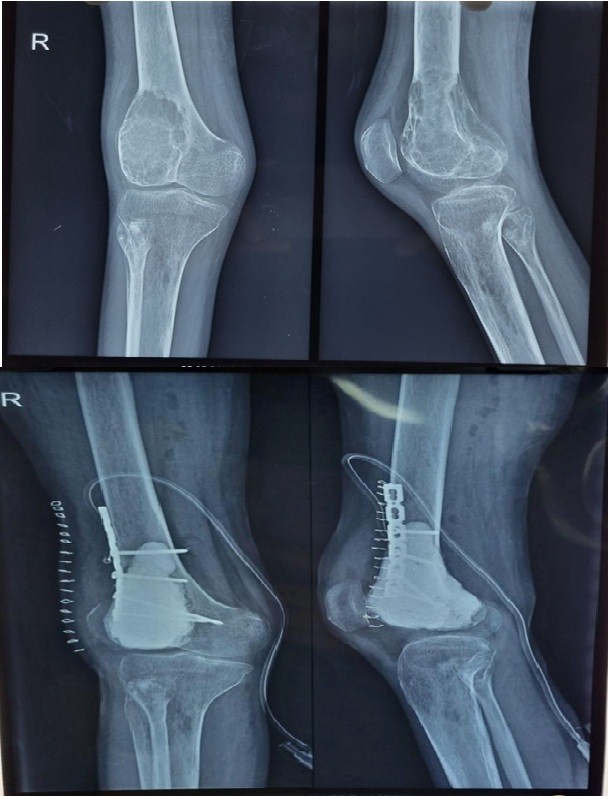

Figure 5: Curettage and bone cement filling of the distal femur skip lesion with supplementary fixation.

The distal femoral lesion was treated with curettage and bone cement filling (Fig. 5). In addition, a plate was applied at the distal femur for reinforcement. The patient was allowed to bear weight with a walker 21 days postoperatively. Gradually, she demonstrated significant clinical improvement, regaining the ability to bear weight without pain or support. A repeat HRCT of the chest showed regression of the small lesions. Postoperatively, denosumab was continued for 4 months as a monthly dose. Follow-up imaging over 12 months revealed no evidence of recurrence, and laboratory parameters remained within normal limits (Fig. 6).

Figure 6: 1-year follow-up of the case showing no recurrence with good fixation.